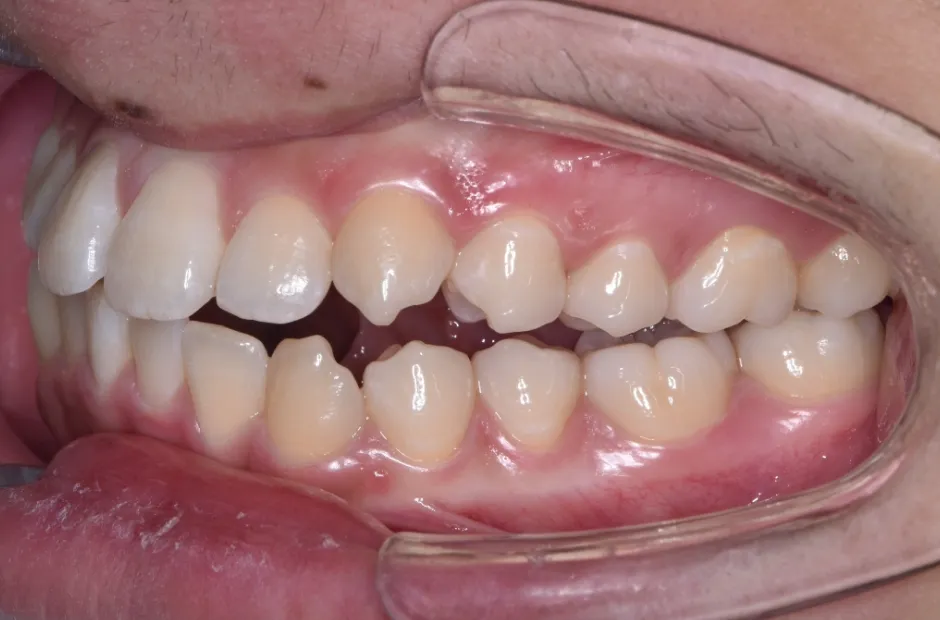

| 診断名・主訴 | 下顎前突、叢生 |

|---|---|

| 年齢・性別 | 23歳・女性 |

| 治療期間・回数 | 3年 |

| 治療に用いた主な装置 | 上顎5,5 下顎4,4 |

| 抜歯部位 | 舌側矯正 |

| 治療費 | 100万円(税抜) |

| リスク・副作用 | 装置による違和感・疼痛・歯肉退縮・歯根吸収・虫歯のリスクなど |

治療前

治療後